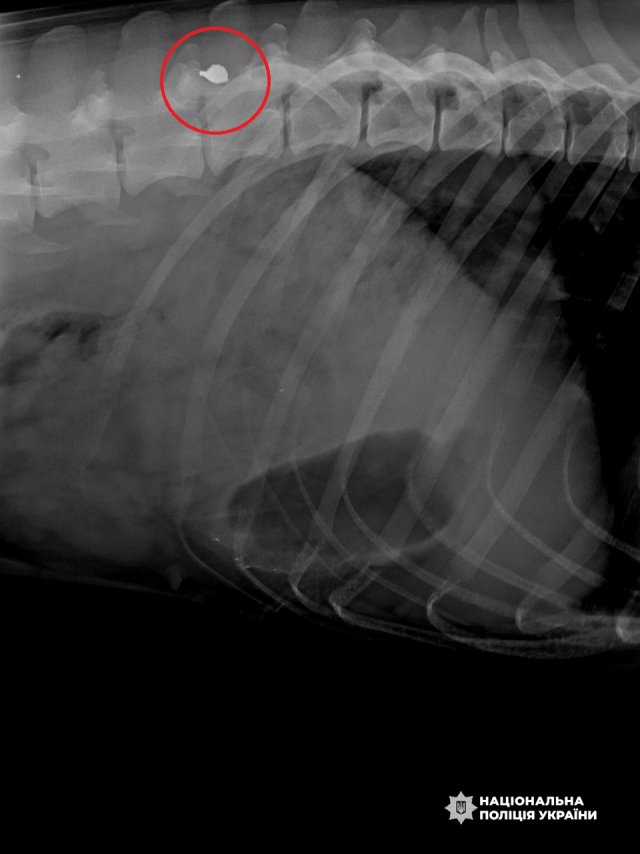

До медичного закладу їх евакуювали колеги. Олег дістав вогнепальні поранення обличчя й руки. У Фані ж ветеринари діагностували контузію, уламкове поранення біля хребта, порізи живота й носа. Шлях лікування і реабілітації був непростий, та вони все витримали.